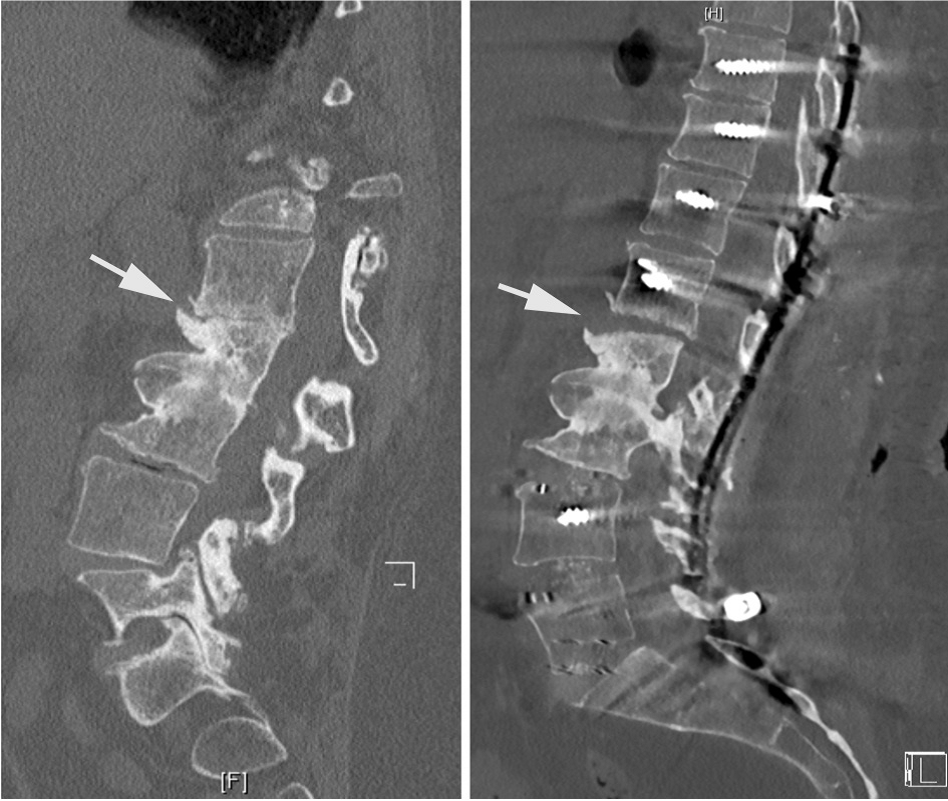

如果术后患者在随访过程中出现疼痛,并且X光片显示内固定棒断裂,则应高度怀疑脊柱出现不愈合的情况。在判断节段不融合时,应不断强调内固定棒在单一节段上发生断裂,并不代表仅存在该节段的脊柱不融合,应警惕多节段不融合的风险。所有脊柱节段均应在影像学上进行仔细检查,并在术中进行探查,以避免多次的翻修手术。文中,作者还特别强调了Ponte截骨在应用此类患者时的注意事项。Ponte截骨术在当通过有力的加压对节段性后凸畸形进行矫正时,前方骨赘可能会出现破裂,导致前方狭窄的椎间隙张开。此时,必须通过前路支撑与植骨来稳定这些节段,以防止术后矫正丢失与不融合情况的发生。如果已经发生,则建议使用OLIF进行前路的支撑融合。

Ponte截骨使狭窄的间隙在前方张开,后期可能缺乏良好的前柱支撑出现不融合

作者在文中描述避免不融合与内固定棒断裂的方法时说明,如果固定节段包括骶骨与骨盆时,仅仅依赖后方的融合而没有前柱的支撑可能还是不够的。作者仍然建议在前柱采用ALIF或TLIF技术避免不融合或再手术的发生。同时,今年来在针对内固定棒断裂的问题时,双棒技术的应用已表现出良好的临床结果,在文献报道中能够降低不愈合的风险。增加卫星棒的目的在于增加两个额外的内固定棒来加强固定并分担一部分应力,降低单一内固定棒所承受的应力。